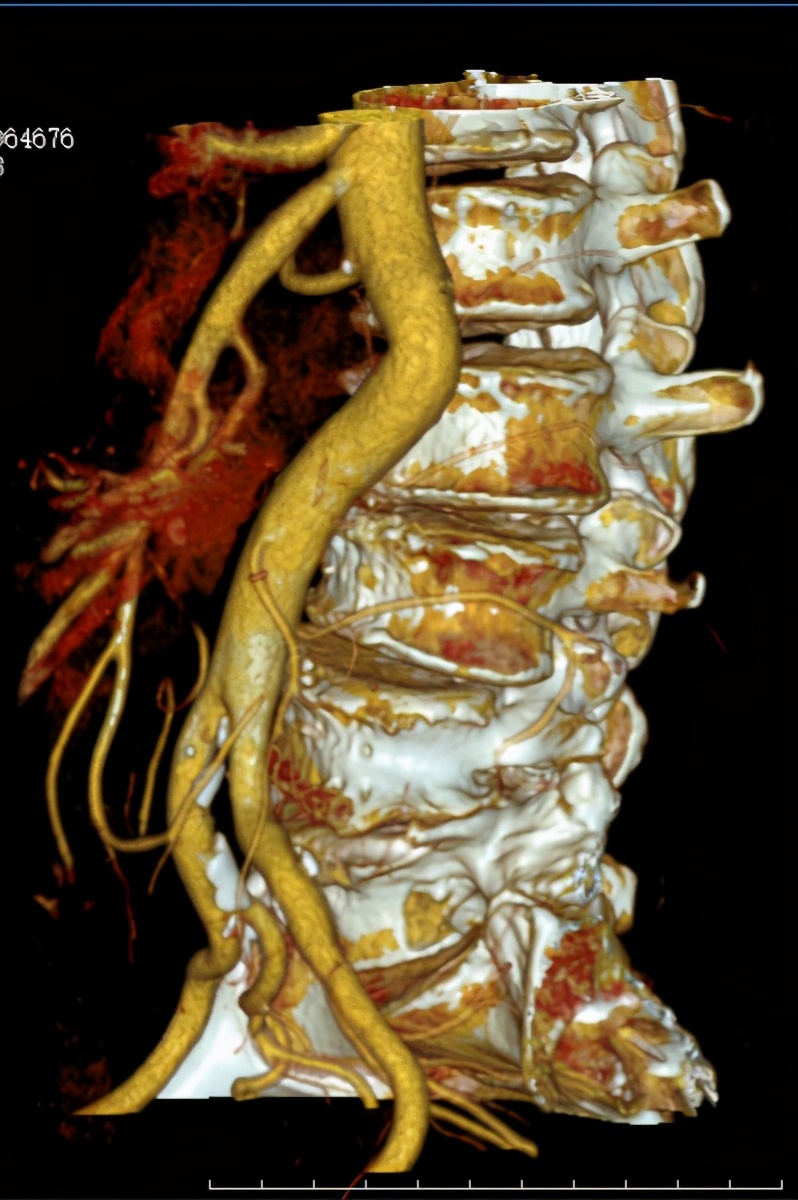

术前CT及MRI检查发现腰5/骶1椎管及左侧神经根管、椎旁软组织肿块